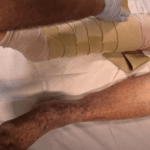

Because we are in the hospital and we dont have access to a washing machine a oversized tubular bandage was used to protect the FarrowWrap from the cream and exudate. ** NO COMPRESSION IS TO COME FROM THE BANDAGE ** Please make sure the tubular bandage goes above where the FarrowWrap will begin. This is for comfort.

FarrowWraps are designed to mimic compression bandages and they are designed with a 50% bandage overlap already. All you are doing to tightening the straps to a comfortable level for the patient. Compliance is the key here. Some pressure, even if its not at the appropriate level, is better than none.